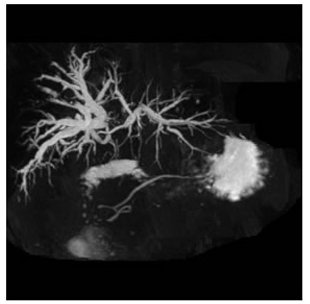

MRCP showing type III b hilar tumor